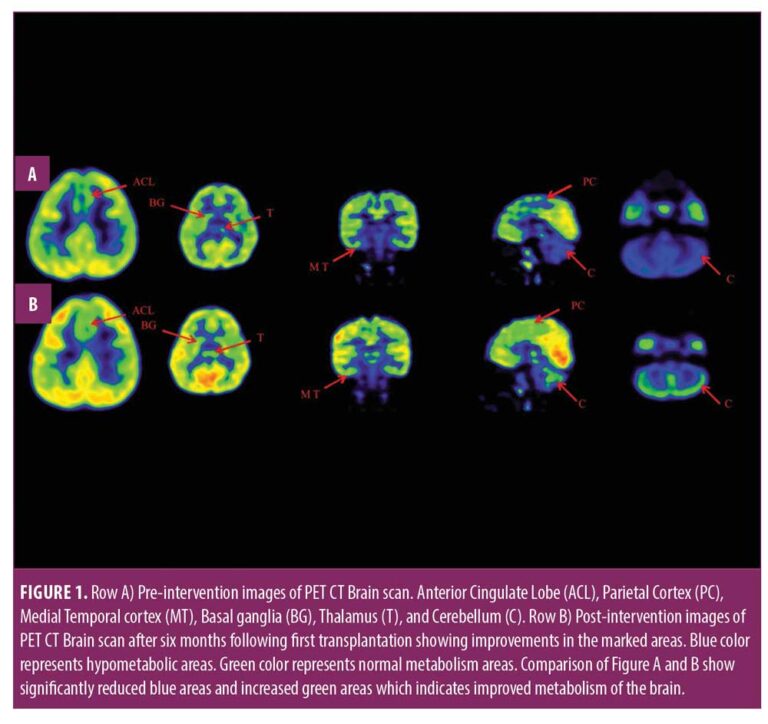

本報告中,我們治療了一名患有痙攣性雙癱性腦癱的兒童,在對康復反應有限后,采用了多種細胞療法。臨床改善的結果與客觀(guān)量表相關(guān),例如粗大運動(dòng)功能測量 (GMFM)、粗大運動(dòng)功能分類(lèi)系統 (GMFCS) 以及功能獨立測量 (FIM) 和 (PET CT) 腦成像研究。

在認知上,由于他定期上學(xué),他的注意力持續時(shí)間和坐姿耐受力也得到了改善。GMFM分數從60.67提高到67。GMFCS等級由3級提升至2級;FIM評分從97分提高到99分。比較第一次細胞治療之前和之后7個(gè)月期間進(jìn)行的腦部PET CT掃描結果,發(fā)現前扣帶回葉、頂葉皮層、內側顳葉皮層、丘腦、基底神經(jīng)節和小腦(表1)。

在此,我們通過(guò)客觀(guān)量表(如FIM、GMFM和GMFCS)和正電子發(fā)射計算機斷層掃描腦神經(jīng)影像對比研究來(lái)監測細胞療法后的療效。在16個(gè)月的治療過(guò)程中,GMFM評分從60.67分提高到81.88分,其中坐的領(lǐng)域從59分提高到60分,爬行和跪的領(lǐng)域從32分提高到40分,站的領(lǐng)域從6分提高到27分,走、跑和跳的領(lǐng)域從8分提高到32分。GMFCS 分級從第3級提高到第2級,因為孩子能夠騰出雙手坐在椅子上,能夠在沒(méi)有幫助的情況下在平整的地面上行走和奔跑,還能夠扶著(zhù)欄桿爬樓梯。FIM分數從91分提高到99分,這表明他的功能狀況有所改善。

這項研究表明,多種干細胞療法結合神經(jīng)康復可有效改善腦癱患者的粗大運動(dòng)功能和功能獨立性。自體BMMNC多次移植后進(jìn)行強烈的神經(jīng)康復可加快神經(jīng)再生過(guò)程,這反過(guò)來(lái)又反映了患者殘疾程度和生活質(zhì)量的積極結果。PET CT掃描可以有效地用于監測干預后細胞水平發(fā)生的變化。因此,多細胞療法是安全、可行的,并且可以有效地與腦癱的神經(jīng)康復相結合作為增強治療。